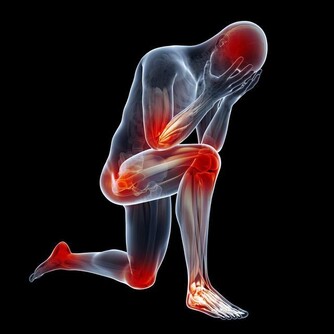

中風往往發病急、病情變化快和死亡率高,即使保住了性命致殘率也高,也會留下口眼歪斜、半身不遂、肢體麻木和語言不清等問題。所以,預防中風對於中老年人來說非常重要。